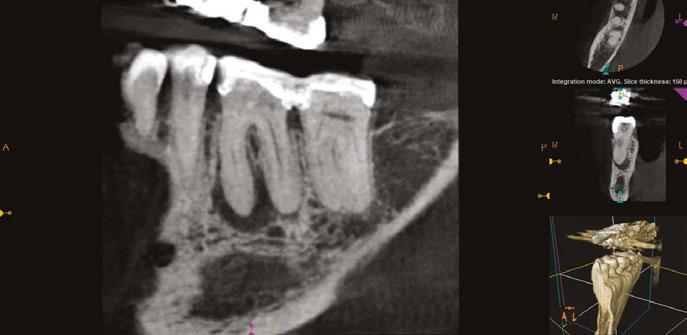

As previous literature has identified the negative effect between periradicular periodontitis of natural teeth and adjacent implants, a limited field of view CBCT (Carestream Dental S 8200 3D, Atlanta, Georgia) was exposed to properly define the periapical radiolucency. Measuring from the apex of tooth No. 11 to a line perpendicular to the long axis of the implant,

5A-5B: CBCT was taken during initial endodontic exam in 2023. 5A. Coronal CBCT

revealed a 6.1 mm x 3.0 mm hypodensity extending from the apical and distal aspect of No. 11. 5B. Sagittal

slices revealed the presence of bone between tooth No. 11 and implant No. 12

spacing of 3.4 mm between the two was noted (Figure 4). The recommended amount of space between a natural tooth and dental implant should be 1.5 mm-2 mm, proving adequate spacing in this case.15 Coronal views of the CBCT evaluation revealed a 6.1 mm x 3.0 mm hypodensity extending from the apical and distal aspect of tooth No. 11 (Figure 5A). Sagittal slices revealed the presence of healthy bone morphology between the distal border of the hypodensity on tooth No. 11 and implant No. 12, thus the hypodensity did not extend to the implant (Figure 5B). Reference was made to the Treatment Options for the Compromised Tooth: A Decision Guide published by the AAE in 2017 to determine prognosis.16 In evaluating the coronal tooth structure, tooth No. 11 had a well-fitting crown with adequate margins, no need for crown lengthening, and required only routine endodontic treatment placing it in the favorable category. The periodontal condition of tooth No. 11 was also favorable with probing depths equal to or less than 3 mm and a normal periodontium. Lastly, the apical periodontitis was expected to resolve following non-surgical root canal treatment.16 Thus, tooth No. 11 was diagnosed as pulpal necrosis with asymptomatic apical periodontitis with a favorable prognosis. Nonsurgical root canal treatment was planned, and informed consent was obtained.

Figure 4: Sagittal CBCT slice revealed 3.4 mm of space between the apex of tooth No. 11 and the mesial border of implant No. 12

Figures

slice

CBCT